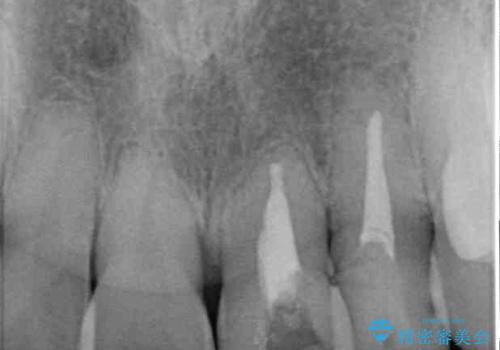

- 前歯の反対咬合により、日々強い痛みを感じているとのことで来院された患者様です。

骨格的に下顎が前方位にありますが、歯列矯正で前歯の被蓋関係を改善することができると判断されたため、インビザラインにより矯正治療を行うこととしました。

また、上顎前歯と下顎大臼歯に神経を取り除いた歯があったため、矯正治療後に、セラミッククラウンにて補綴することとしました。

前歯が内側に倒れ込む力がかかり、正常な歯ぎしりもできないため、非常に負担のかかりやすい咬み合わせでした。